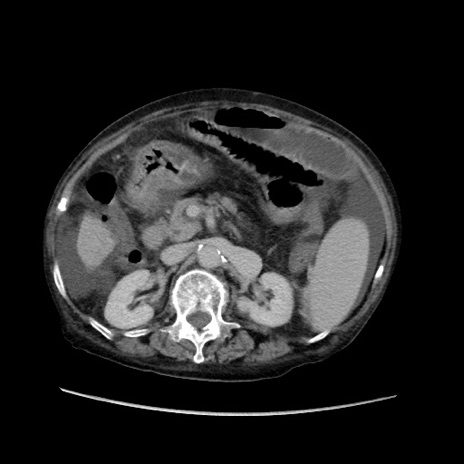

症例31(横断像)

【症例】80歳代 女性

【主訴】腹部膨満感

【現病歴】他院にて肝硬変にてフォロー中。1週間前から便秘、腹部膨満感、臍部腫瘤あり受診となる。

【既往歴】肝硬変

【身体所見】腹部膨隆あり、皮膚変化なし、疼痛なし。

【データ】WBC 4600、CRP 0.25